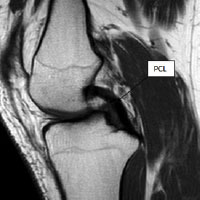

Figure 1: magnetic resonance imaging (MRI) scan showing native posterior cruciate ligament (PCL) connecting femur (thighbone) to tibia (shinbone)

The posterior cruciate ligament (PCL) is one of the less commonly injured knee ligaments. Like the anterior cruciate ligament (ACL) it connects the femur (thigh bone) to the tibia (shin bone) (see fig. 1). Its main role is to keep the knee stable during rapid acceleration and deceleration activities.